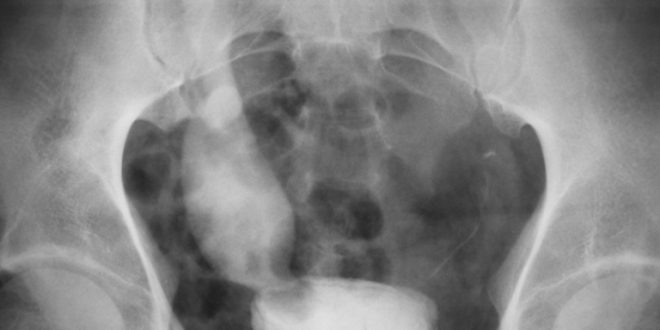

Los síntomas más comunes cuando una persona empieza a padecer cáncer de la vejiga son problemas como el dolor y la obstrucción urinaria (dificultad para orinar). Cuando se presentan estos síntomas, el paciente deberá hacerse una cistoscopia, para inspeccionar el interior de la vejiga y de la uretra. De esta forma se pueden detectar irregularidades e iniciar un tratamiento.